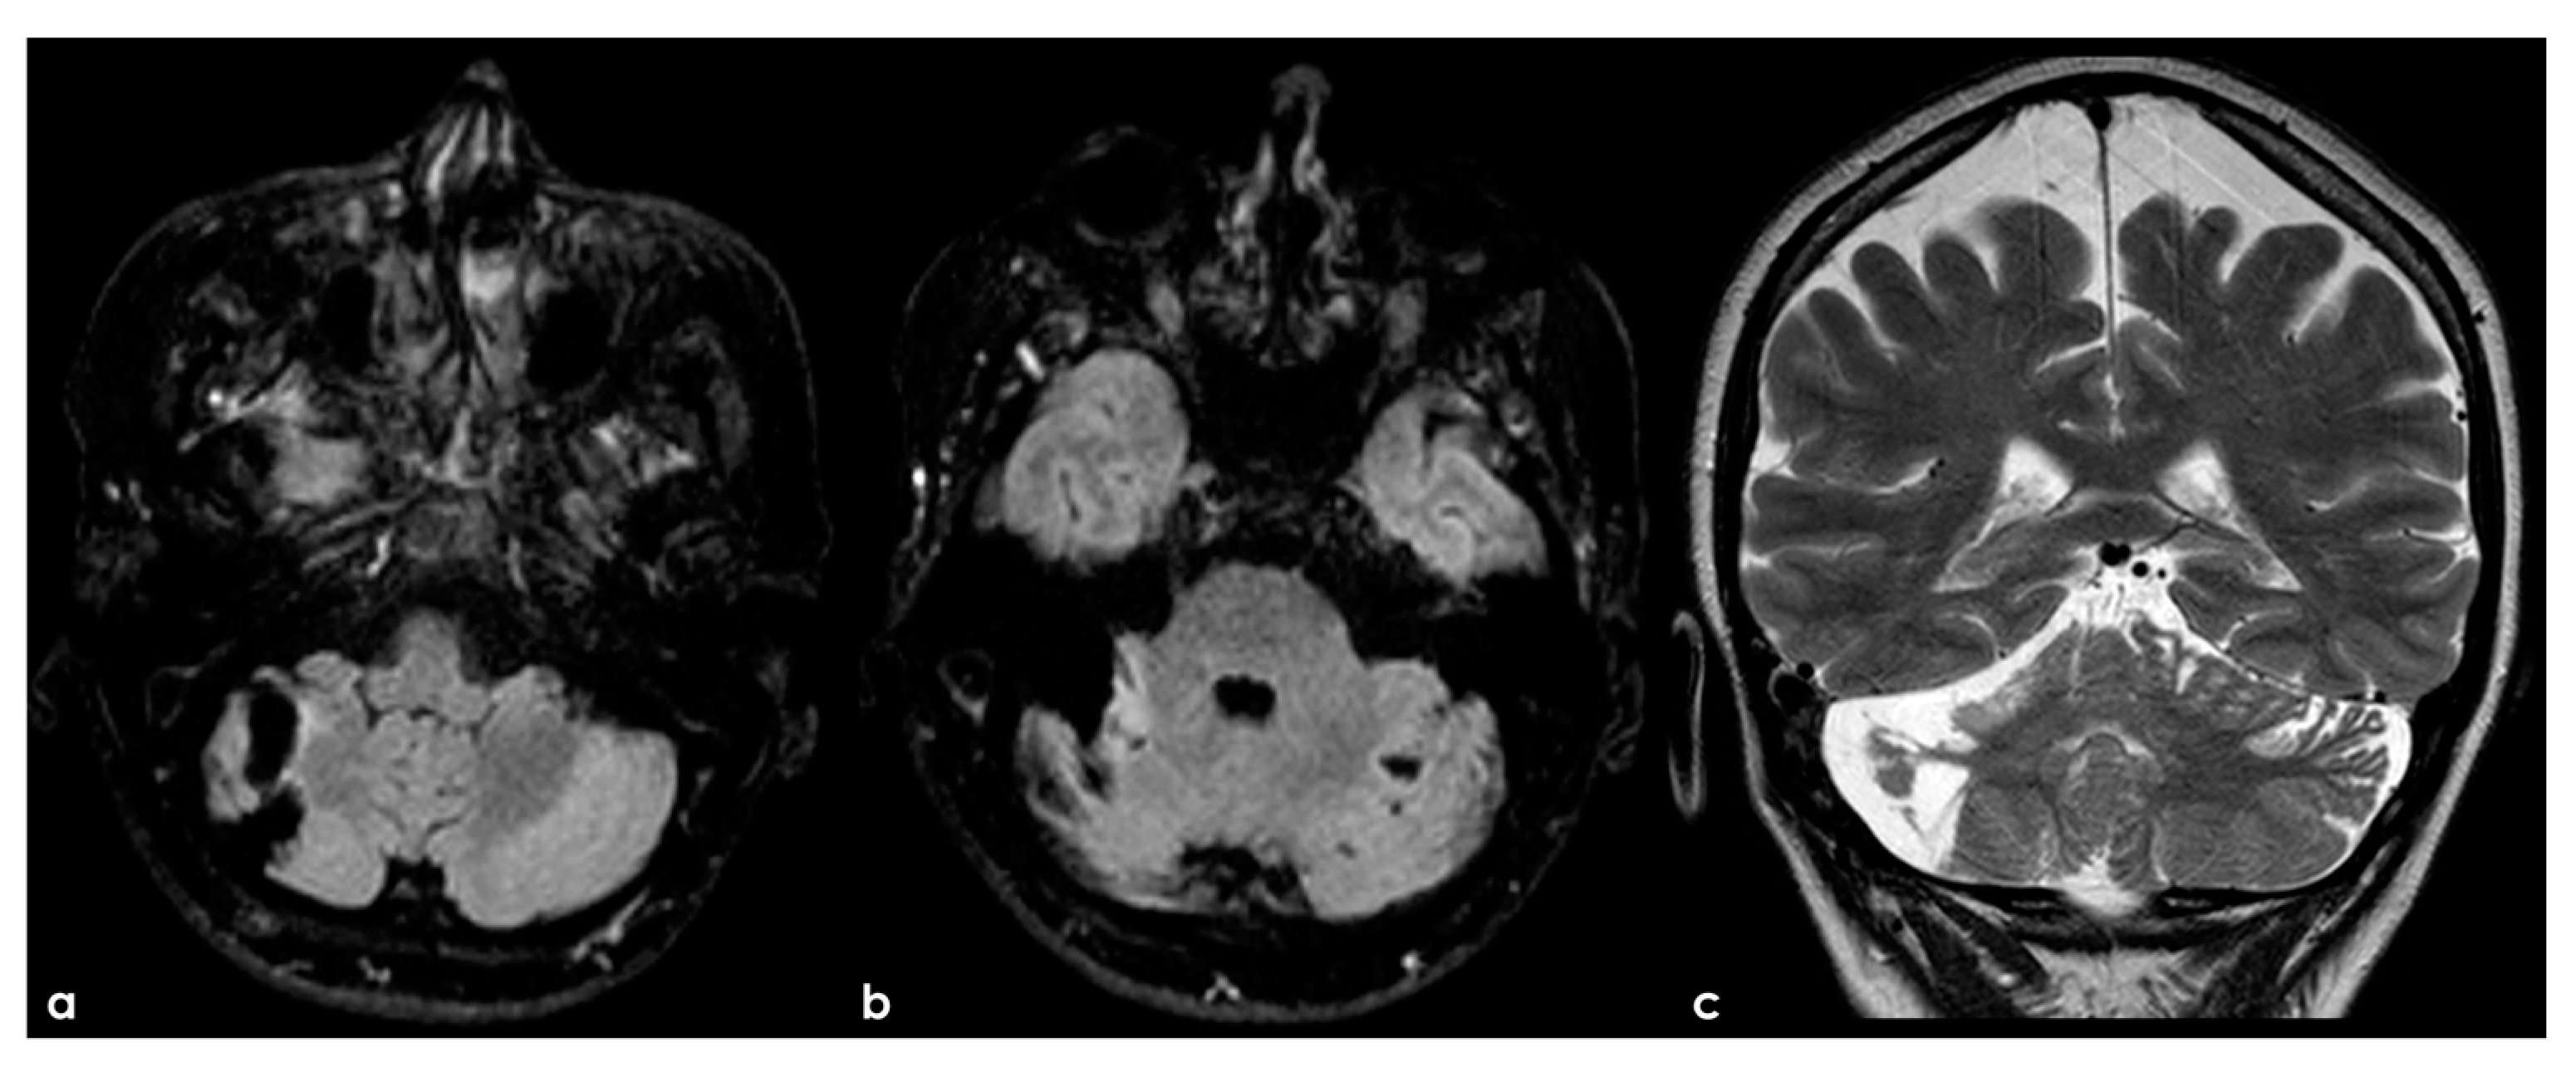

4.2.3. Brain Parenchyma